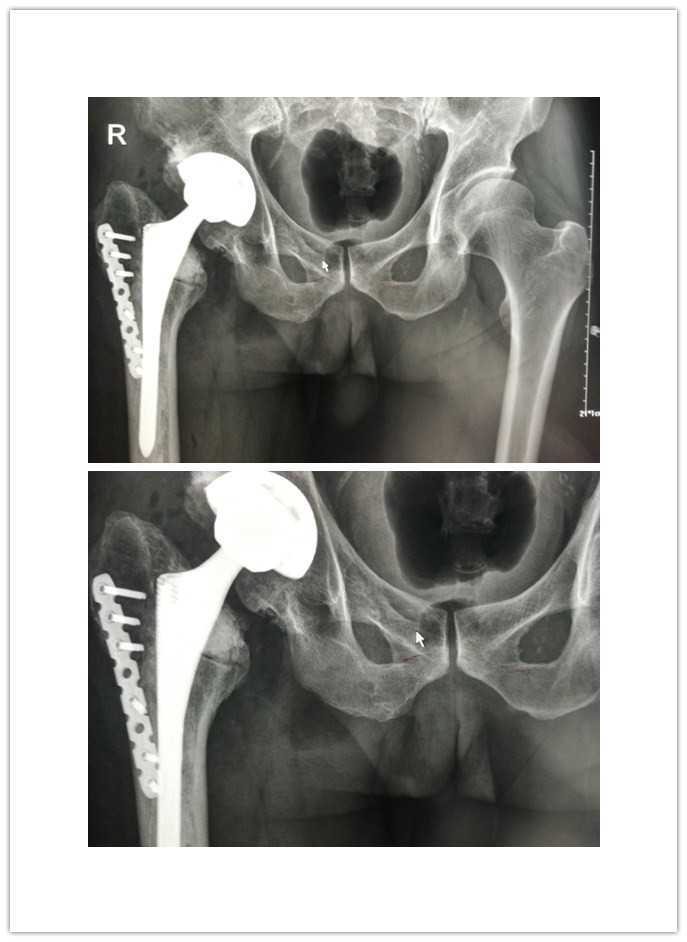

患者王先生,63岁,因半月前不慎摔伤右下肢,在家休息后疼痛加重,遂来我院就诊。骨一科刘波主任接诊后,详细询问其过往病史,得知患者29年前因右侧股骨颈骨折,在济南某医院行右侧人工股骨头置换术,术后右下肢行走良好;但8年前,右髋部疼痛复发、跛行愈加厉害;加之此次摔伤,致使病情加重。经X线检查示:右侧股骨头置换假体下沉,右腓骨远端骨折;且查体后发现其右下肢较左下肢短约5cm。刘主任考虑到王先生年岁已高,且体内假体已有29年,早已超出使用年限,遂决定为其行右侧人工髋关节翻修术。

术后,刘主任及时为患者量身制定了功能康复锻炼方案,在骨一科医护人员的精心指导下,王先生右下肢功能逐渐恢复。X线检查示:右髋部假体位置良好,力线良好;经术后测量右下肢较左下肢长度相差1cm,基本恢复双下肢等长。术后14天,王先生已能够拄拐下地行走,并顺利拆线出院。该手术的成功标志着我院骨一科在我县骨科临床技术领域获得质的突破。